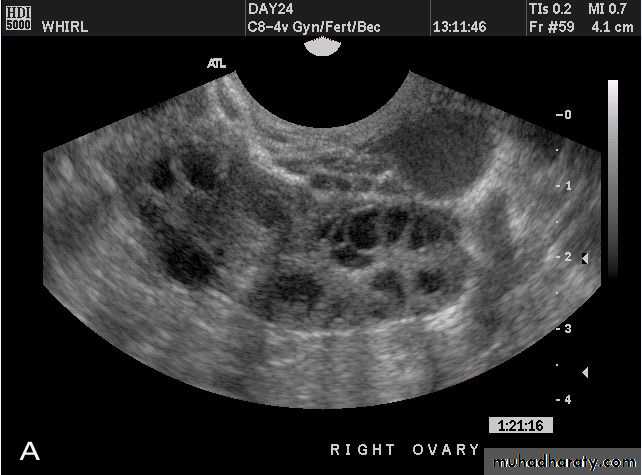

Ovarian hyperstimulation syndrome (OHSS):

This young adult female patient was examined to evaluate the uterus and ovaries. She was under treatment for infertility and was using gonadotropins. Ultrasound images of the ovaries show grossly enlarged ovaries with large cysts (measuring 2.6 to 3 cms.) in both ovaries. These ultrasound findings are diagnostic of OHSS or ovarian hyperstimulation syndrome.

• Ovarian hyperstimulation syndrome (OHSS):

The ultrasound image again show hyperstimulated ovaries. Both ovaries are grossly enlarged and cystic.